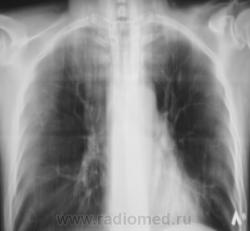

Контроль после флюорографии.

После курса лечения.

После лечения динамика очень хорошая.

А сейчас, если не ошибаюсь, есть свежие очаги слева?

Я тоже отметил "свежие" очаги, но они появились на "фоне" курса лечения.